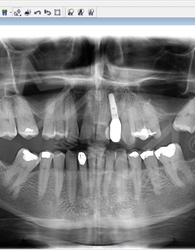

來到深圳,多方尋醫,一個醫生朋友告訴我,這個只有到麥芽找鄭蒼尚院長,他能做。 “我有6個月一直沒有牙齒,我要我的牙齒。”這是我見到鄭院長後說的第一句話,在麥芽流程很順利,經過拍片檢查後,鄭院長說我剩餘殘根反復發炎鬆動,牙槽骨受損嚴重,影響咀嚼功能,只能拔除殘根後需引導骨組織再生,不能一期種牙…. 很專業的詞我不太懂,但是他能處理我就放心了!

今年的4月18日,我去了第一次複診後,直接飛回了加拿大。 坐飛機過程也沒有什麼不適感,而且有按照鄭院長的要求,一直在好好的呵護我的種植牙。 現在回到中國,手機上顯示客服的複診簡訊提醒,雖然在還未種完牙的情况下,但這絲毫不影響我繼續享用美食。 複診的時候,拍了片子,鄭院長說植入的植體與骨結合不錯,然後給我安裝了癒合基臺,說我有什麼不適的話,都可以過來 。